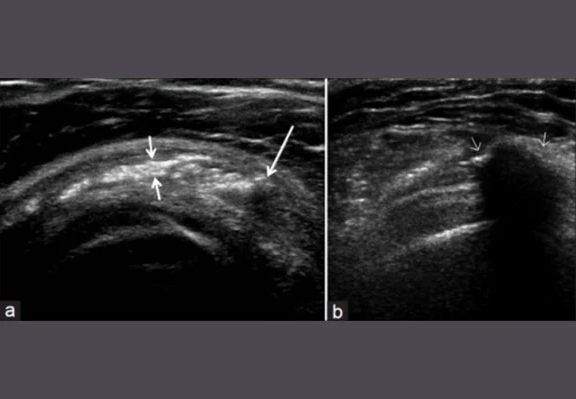

Ultrasound/ X-ray or MRI can be used to confirm diagnosis

Image from OpenI – Licensed by CC